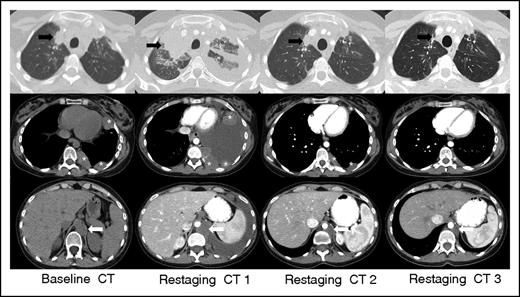

IR(1): Restaging CT 1 at 3 weeks demonstrates overall progression of tumor burden (SPD +124% from baseline) as evidenced interval increase in a right upper lobe lung mass (black arrow), left-sided pleural masses (asterisks), and left retrocrural lymphadenopathy (white arrow), and interval development of a large left-sided pleural effusion. Subsequent follow-up at 7 weeks (restaging CT 2) shows an interval decrease in size of all lesions with resolution of the left pleural effusion (SPD −27% from baseline). Additional follow-up at 13 weeks (restaging CT 3) demonstrates a further interval decrease in tumor burden, and the patient achieved a PR by revised response criteria (SPD −54% from baseline) with clear subsequent clinical benefit from continued treatment.

1. Increase in overall tumor burden (as assessed by sum of the product of the diameters [SPD]) of ≥50% of up to 6 measurable lesions in the first 12 weeks of therapy, without clinical deterioration [IR(1)] (Figure 3).